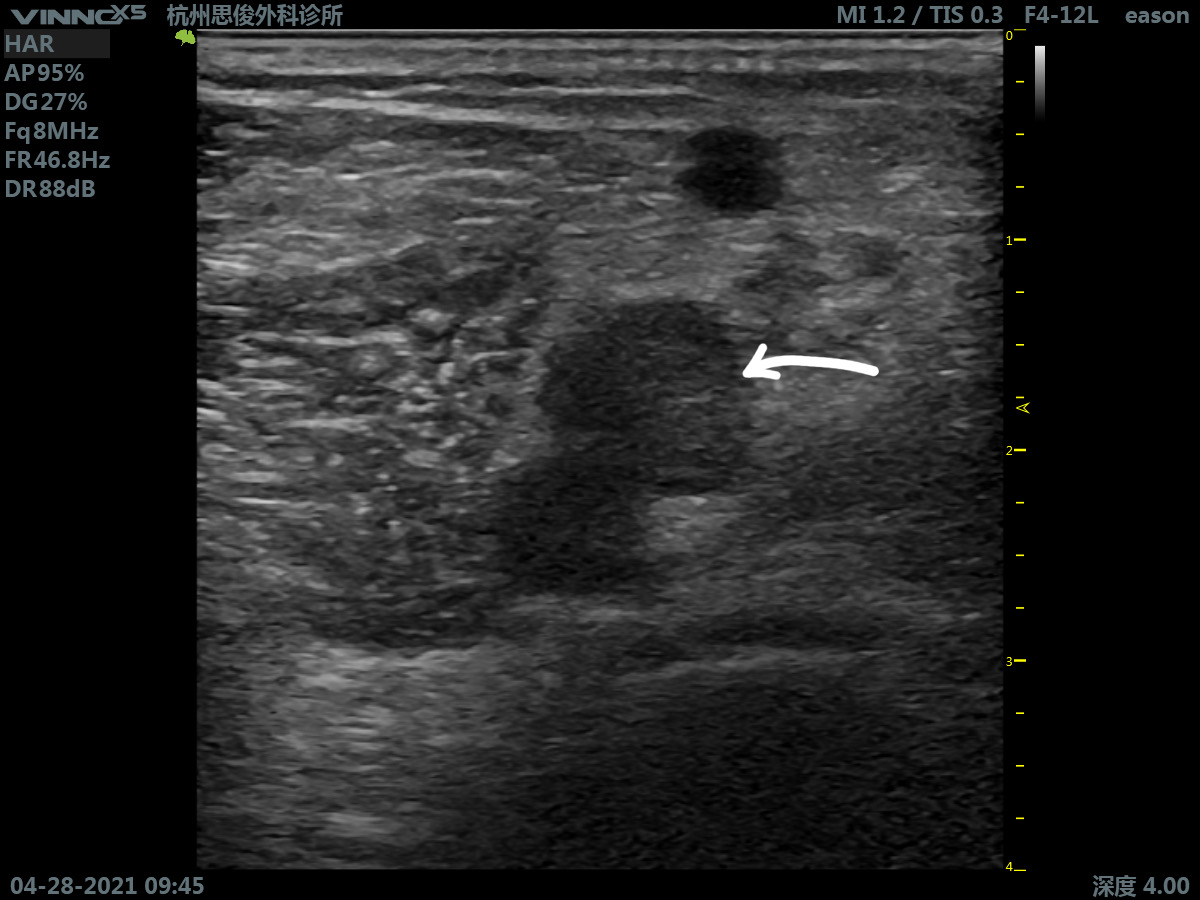

超声筛查发现患者右侧股静脉、膕静脉、腓肠肌内侧静脉内均有混合回声影填充且无法完全压闭,与之前(2019年)在当地医院超声看到陈旧性血栓的部位基本吻合。

回到病例 ,仔细辨别还可以发现:股静脉内呈高回声影,但是管腔可以被部分闭闭,而膕静脉和腓肠肌内侧静脉腔内呈低回声填充,血管扩张,管腔完全不能压闭。患者急查D-二聚体明显升高,结合其临床症状,判断其深静脉血栓复发,复发部分在膕静脉和腓肠肌内侧静脉内。